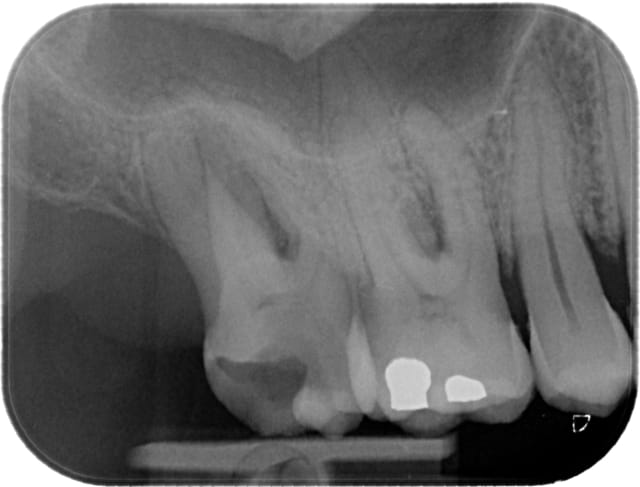

Premier "cas" au wave one... mieux quand j'aurai l'occasion !

Test moi 1962 03 22 x 2011 04 07 19 10 38 3 pkylym - Eugenol

C'est quoi le petit truc au bout du distal ? je vois mal: de la gutta tire bouchonnée ou un fragment d'instrument

Marc Apap écrivait:

-------------------

> C'est quoi le petit truc au bout du distal ? je vois mal: de la gutta tire

> bouchonnée ou un fragment d'instrument

C'est le cone qui s'est plié en deux ! Je l'ai mis une première fois, ça dépassait de deux mm, je l'ai remis une seconde fois, oh tiens c'est bizarre il va bien maintenant ;)